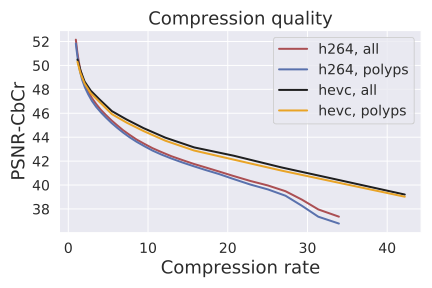

Compression quality: Figure 1 (middle) shows the compression rate versus frame quality distribution for H264 and HEVC. Importantly, we see that H264 and HEVC compress the most medically relvant frames statistically significantly worse: treating each QP value separately, a two-sided Kolmogorov-Smirnov test between distribution of PSNR-CbCr shows that the frame quality is lower for polyp frames than for all frames. For each QP value, , , H264 (HEVC) maximum p-value over all tests is (), mean test statistic (). For the same test with PSNR-Y, see the Appendix. Figure 2 top two rows show the lowest quality compressed frames inside the body according to PSNR-CbCr, with and without polyps (for the absolute worst quality compressed frames, see the Appendix).

Detector performance: Figure 1 (right) shows the polyp detector performance as a function of compression rate. Videos can be compressed by factors of 4.7x and 7.3x before dropping below 99% the base performance for H264 and HEVC respectively, 10.6x and 20.8x for 95%, and 14.3x and 30.4x for 90%. In addition to getting better frame quality and higher compression rates, the detector performs 0.057 AUC better and a 29% relative improvement111relative improvement defined as on HEVC videos compared to H264, as the same compression rate. The same holds in the “practical" regime of compression rates that achieve at least 95% the AUC of the original model: AUC is on average 0.26 AUC improved with a 23% relative improvement in AUC.